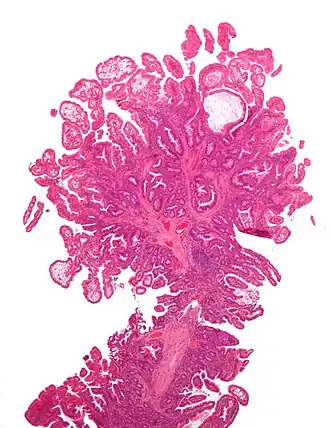

een peutz-jegherstype poliep uit de darm op kleine vergroting | ||||

Het syndroom van Peutz-Jeghers[4][5] is een zeldzaam erfelijk syndroom dat wordt gekenmerkt door poliepen verspreid door het gehele spijsverteringskanaal en door kleine bruine pigmentvlekjes op het slijmvlies van de mondholte, rond de lippen, op het gezicht, de geslachtsdelen en de handpalmen. De poliepen zitten in 25% van de gevallen in de maag, in 30% in de dikke darm en in 100% in de dunne darm. De poliepen zijn geheel onschuldig, maar het syndroom geeft ook een verhoogde kans op kanker, onder andere van de borst, long en eierstokken.